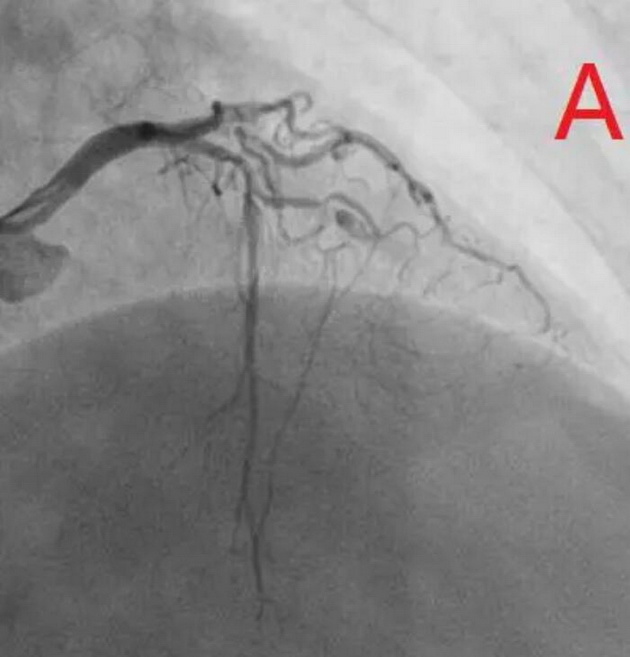

患者为77岁女性,因冠心病进行冠状动脉介入治疗,造影发现冠状动脉前降支不仅闭塞(图A),而且伴有钙化。通过不懈的努力,将闭塞的血管打开,但钙化处球囊无法将病变充分扩张(图B),意味着无法通过植入支架来维持血管管腔。于是采用血管内超声对病变处进行检测,显示病变处存在严重的360度环形钙化(图C、D)。